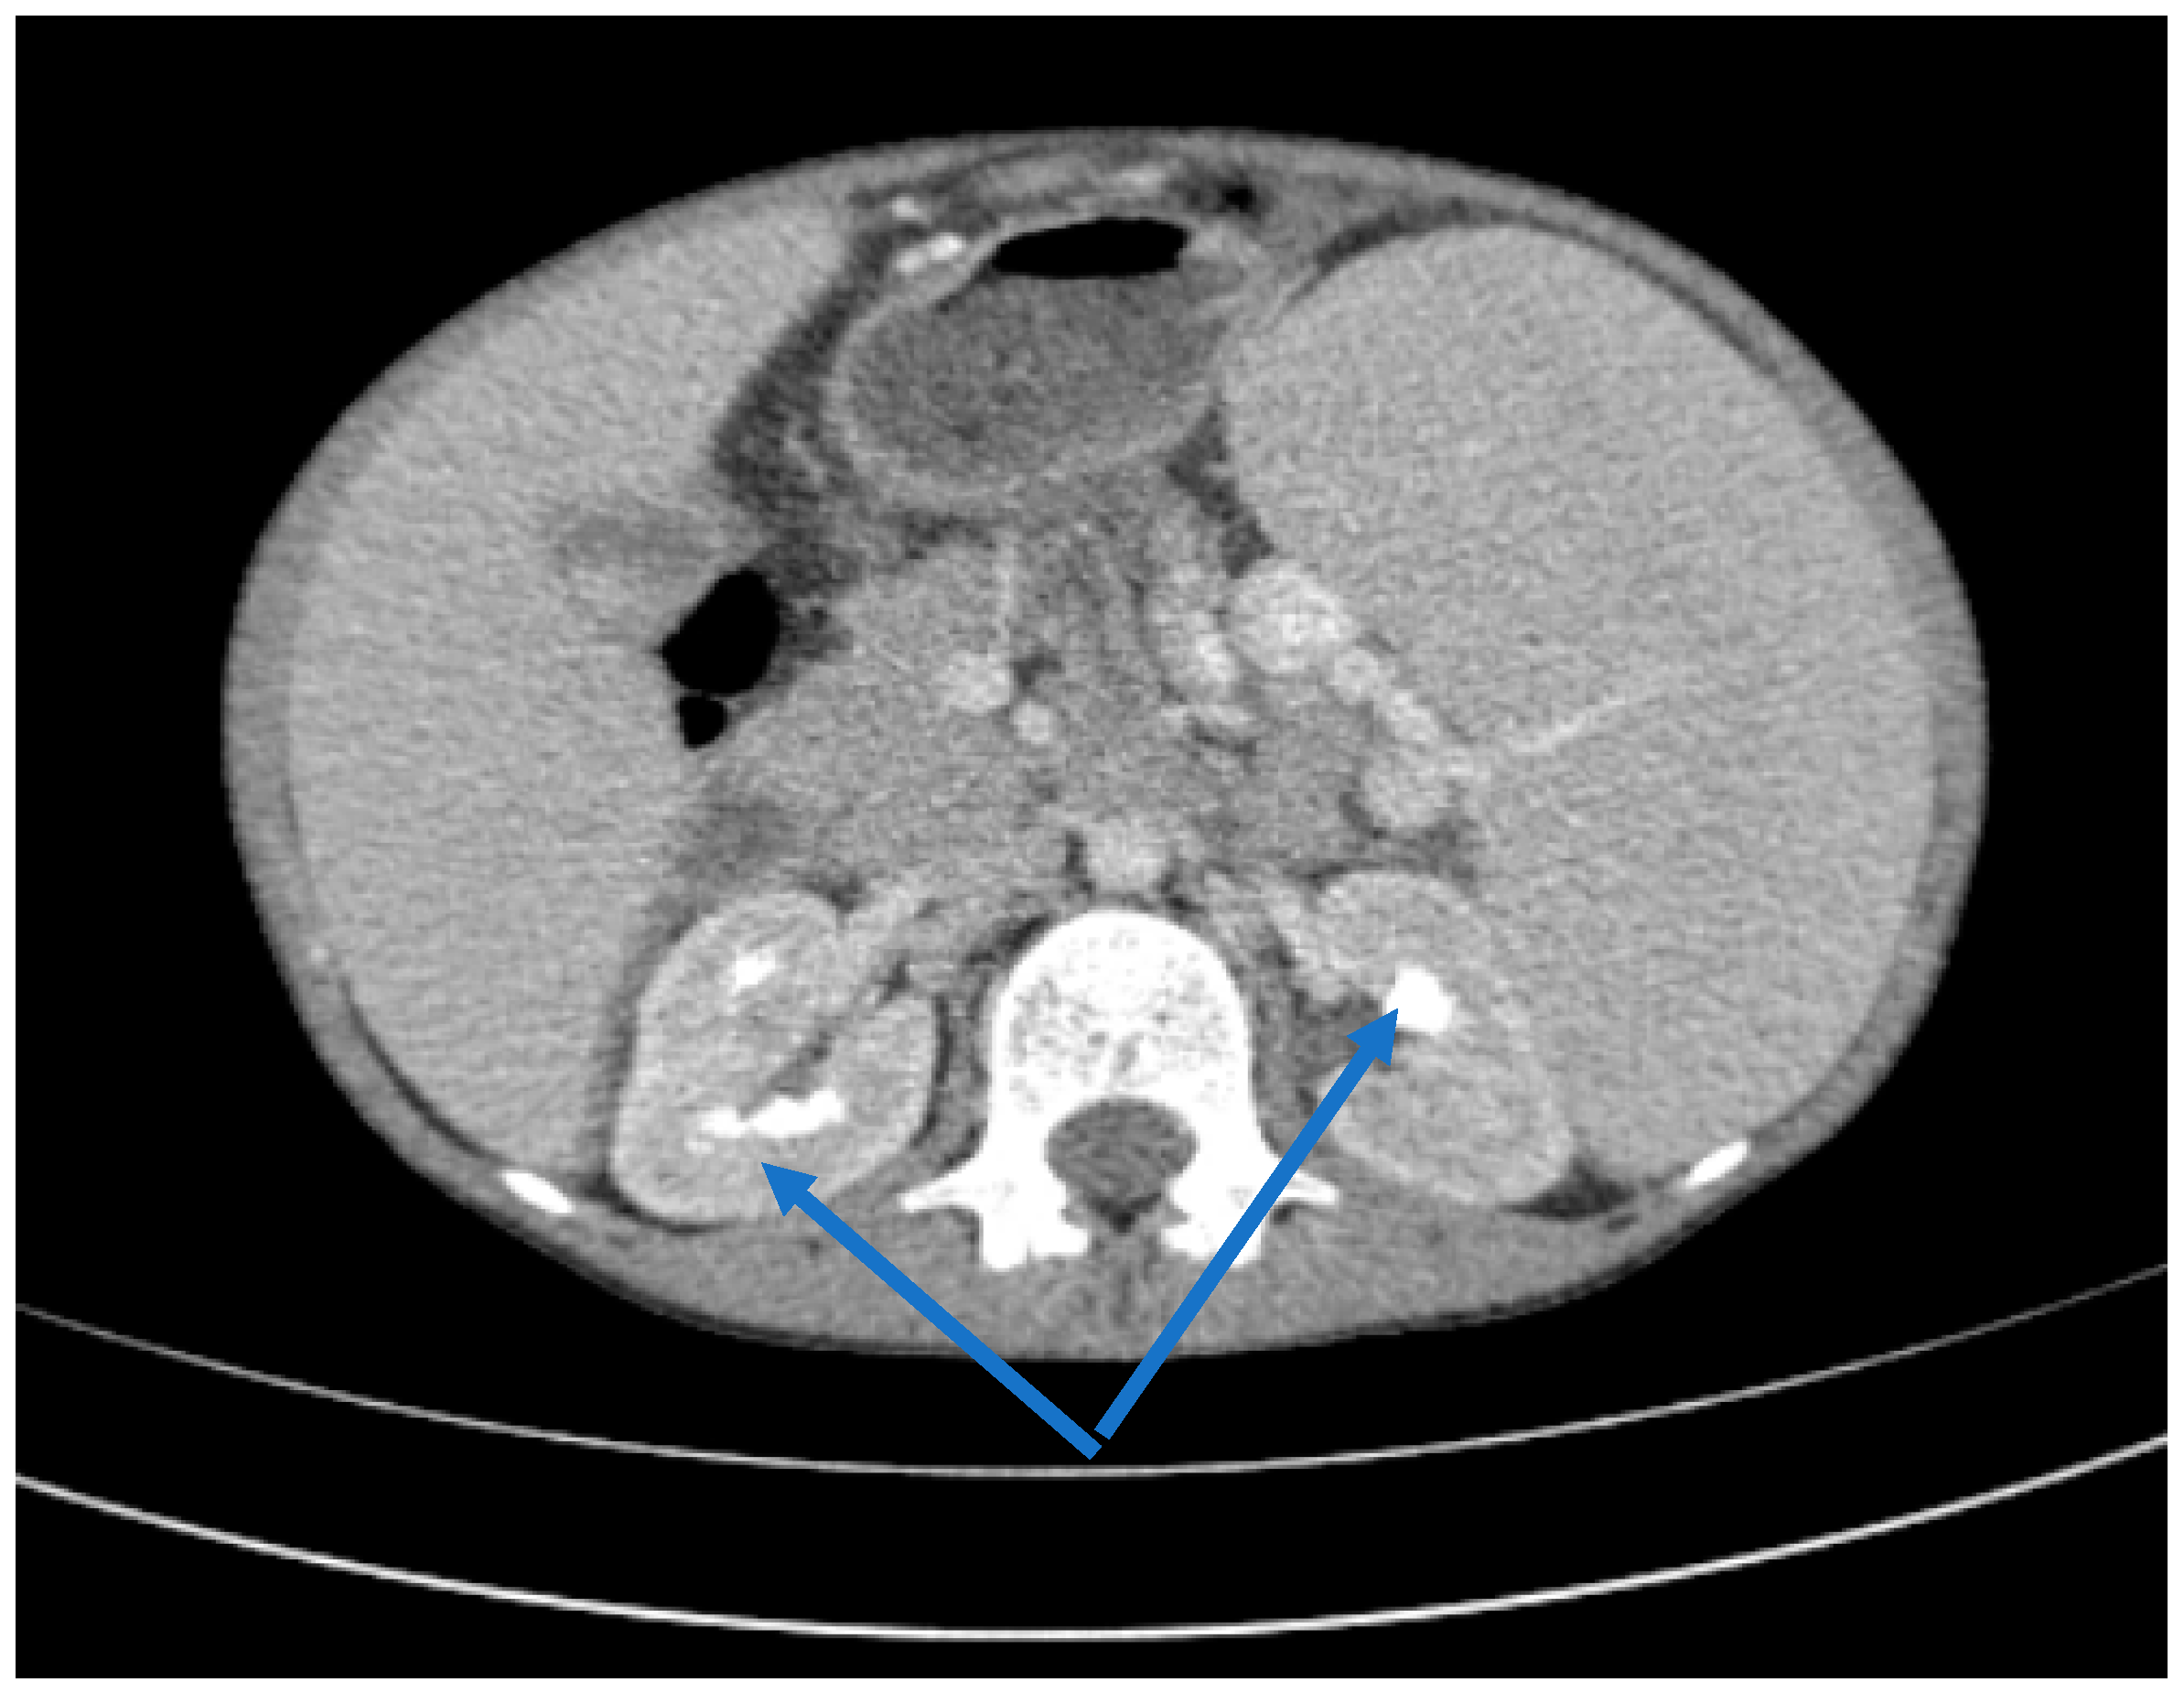

Renal function deteriorated rapidly to a creatinine clearance of 10 mL/min/1.73 m2, requiring the initiation of hemodialysis on day 5 after admission. A history of drug ingestion that could cause acute interstitial nephritis was negative. Serologic tests for Epstein–Barr virus, cytomegalovirus, hepatitis C/B, human immunodeficiency virus, Toxoplasma gondii, and tuberculin skin reaction were negative. In the absence of specific immunological findings, a marked inflammatory syndrome or antibodies such as p-ANCA, c-ANCA or antinuclear antibodies, primary immunodeficiency, a connective tissue disease or vasculitis were excluded. Renal ultrasound evaluation was highly suggestive of nephrocalcinosis. After this preliminary evaluation, the diagnosis of advanced renal disease was made; therefore, the patient started chronic hemodialysis. Thoracic–abdominal computed tomography confirmed renal medullary calcifications, hepatosplenomegaly, hyperdense splenorenal and splenogastric masses as indicators of portal hypertension (Figure 3 and Figure 4).

Figure 4.

Axial CT scans, portal hypertension (blue arrow).